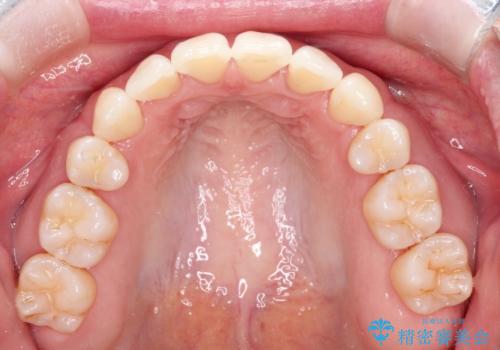

【抜歯ケース】前歯のガタガタをインビザラインで治療

- 前歯のガタガタを主訴に来院されました。

抜歯が必要なケースでしたが、インビザラインでの治療を希望されワイヤーを使用せずに治療を完了しております。

抜歯を伴う矯正治療はマウスピース矯正よりもワイヤー矯正の方がメリットが多いです。当院で抜歯を伴うマウスピース矯正を希望される場合は、場合によってワイヤーを使うことを了承していただいた上で治療を行なっています。